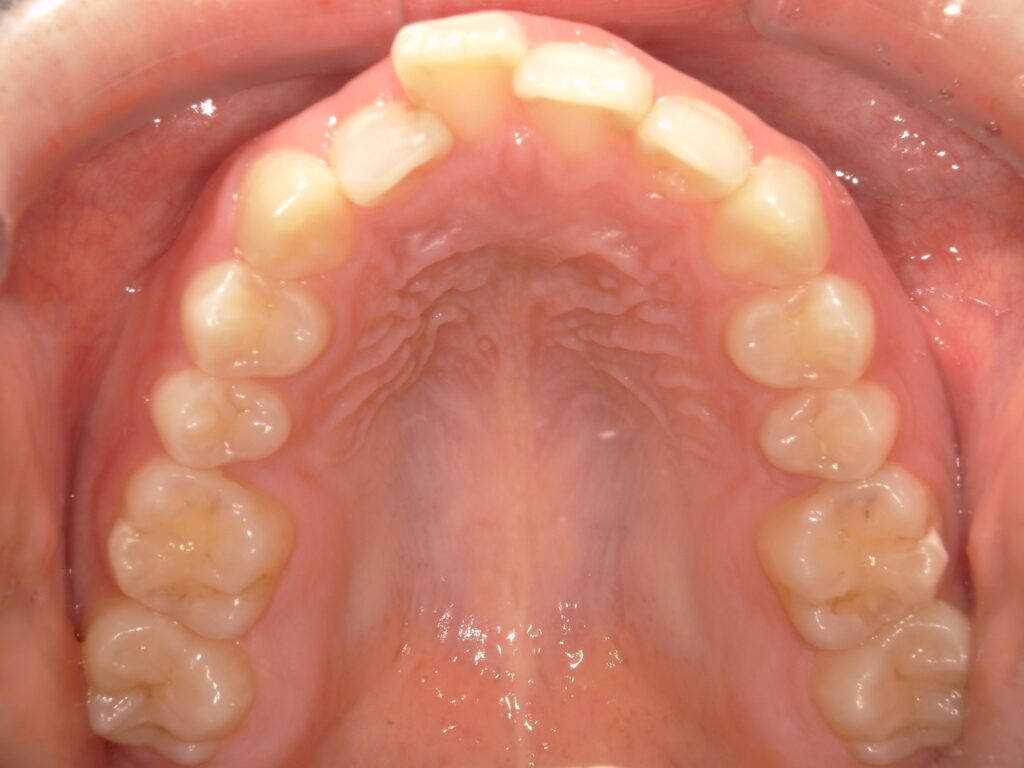

実際に顔に変化が起きた当院の症例を写真で紹介

こちらは当院で矯正治療を行い、患者様のご希望通りの顔貌の変化が起きた症例写真です。

BEFORE

AFTER

症例写真は一例であり、適応や結果には個人差がありますが、適切な診断と治療を行うことでこのような結果を出すことが可能です。